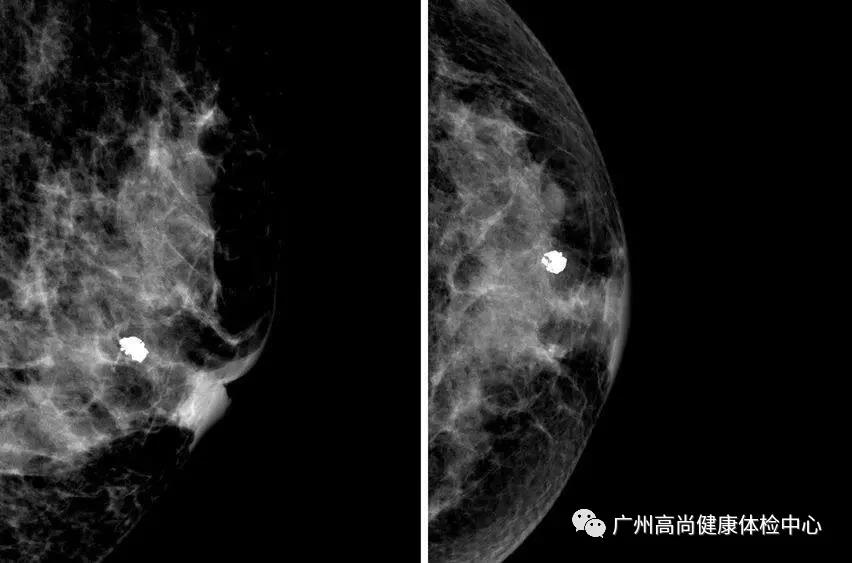

一般來說,若鈣化點比較大顆,沒有群聚簇集的特性,形狀外觀的界線清楚明確,長的均勻、對稱,就屬于良性鈣化點的特征。

乳房的鈣化點大部分都是良性的,或伴有其他良性病變,如乳腺增生。所以,乳房鉬靶上如果看到大大的白點,通常就是良性鈣化點,如纖維腺瘤就常常會在鉬靶的影像上出現(xiàn)爆米花狀的粗糙大白點。

因此,惡性鈣化點的特點是:聚集很緊密,簇聚于局部區(qū)塊,且鈣化點很小,形狀不規(guī)則,每個點都不太一樣,或有針尖狀、小桿狀、分叉狀、簇狀及泥沙樣多屬于惡性病變。